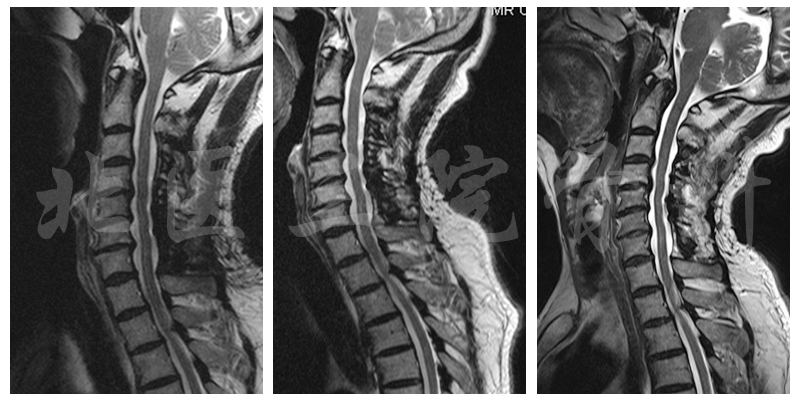

MRI

诊断:脊髓型颈椎病;颈椎间盘突出 (C3-C6);发育性颈椎管狭窄。

随访时影像学检查